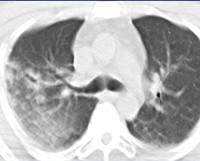

• Рентгенографии или КТ лёгких. Участки инфильтрации лёгочной ткани, соответствующие зоне ушиба, определяются на рентгенограмме через 24-48 часов от момента травмы. Рентгенография позволяет выявить пневмо- и гемоторакс, повреждение костного каркаса. При тяжёлой травме органов дыхания предпочтительнее выполнить компьютерную томографию. Она помогает определить наличие пневмоцеле, ателектазов, отдифференцировать ушиб от разрыва лёгкого.